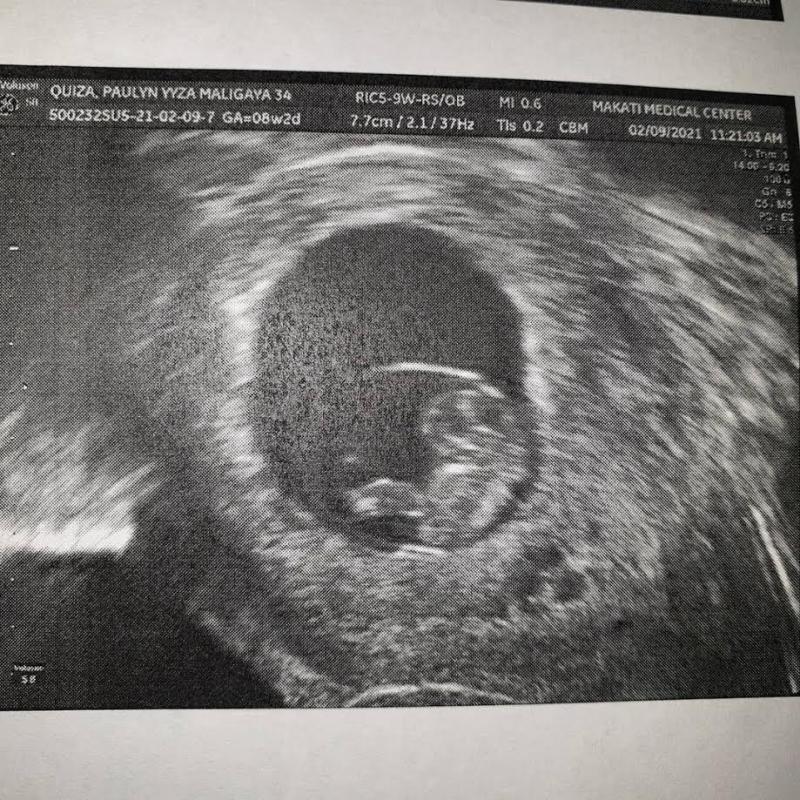

Unang inanunsiyo nina Polo at Paulyn ang paparating nilang baby noong Abril sa Instagram kung saan nag-post si Polo ng ultrasound ng kanilang anak.

Pagbabahagi ng aktor, "Thank you Lord for this Miracle and Blessing. We are excited to meet you Baby P."